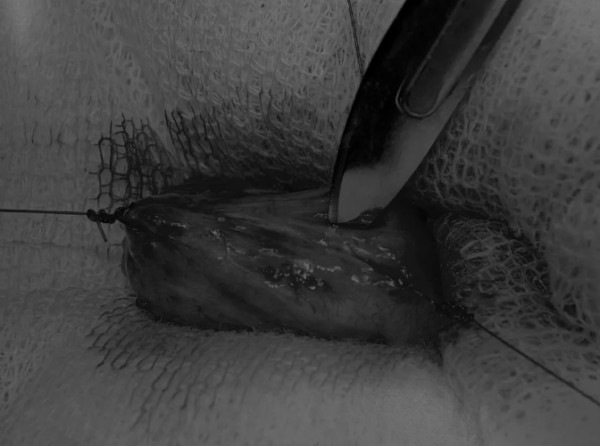

在中线开腹手术后,确定膀胱,将其取出并隔离(图1)。为了使膀胱持续暴露,可在膀胱中线两侧各放置一根固定缝线(图2)。

在牵引缝线之间选择血管扩张较差的区域用手术刀切开膀胱壁(图3)。在牵引缝合线之间用手术刀在血管不良的区域做切口。切开膀胱壁后,膀胱内的手术可按手术方案实施,例如取出结石(图4)。

图3 避开主要的膀胱血管,做一个尽可能小的切口